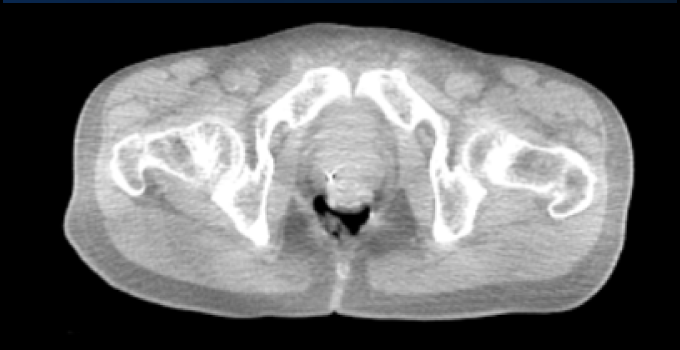

SpaceOAR Vue Hydrogel in different image modalities

Computed Tomography images.

Computed Tomography images*

*Jeff Michalski, M.D. [2020]. Permission granted by Washington University Image.